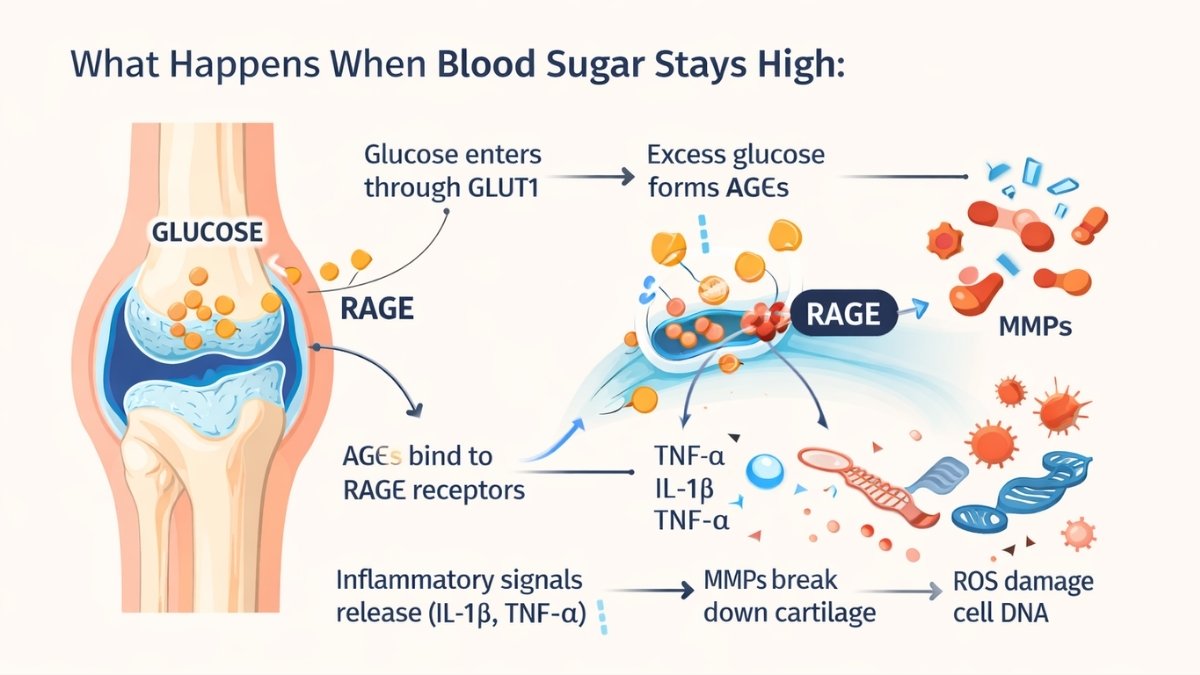

How High Blood Sugar Destroys Cartilage: The AGE-RAGE Connection

Your cartilage cells have glucose transporters called GLUT1. They let sugar in for energy. Normal amounts work fine. But when blood sugar stays high, these transporters become weapons.

Here’s what happens. Excess glucose enters your cartilage cells. It sticks to proteins permanently. These sticky proteins are called Advanced Glycation End Products—AGEs for short. Think of rust forming on metal. AGEs do the same thing to your cartilage. They make it stiff and brittle.

AGEs bind to receptors called RAGE. This triggers an inflammatory explosion. Your cells release TNF-α and IL-1β. These signals tell your body to break down cartilage. Enzymes called MMPs (matrix metalloproteinases) start destroying the cushioning in your joints. At the same time, Reactive Oxygen Species damage your cell DNA and proteins.

What Happens When Blood Sugar Stays High:

- Glucose enters through GLUT1

- Excess glucose forms AGEs

- AGEs bind to RAGE receptors

- Inflammatory signals release (IL-1β, TNF-α)

- MMPs break down cartilage

- ROS damage cell DNA